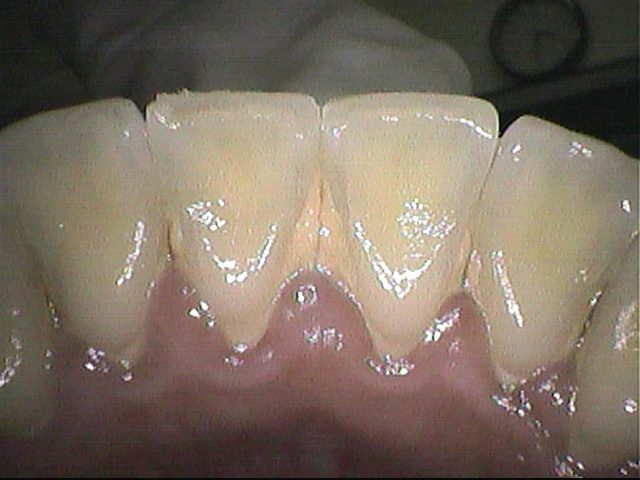

クリーニング前

この方は約3年ぶりのクリーニングで、

下の前歯の間から根元にかけて歯石が多くついていました。